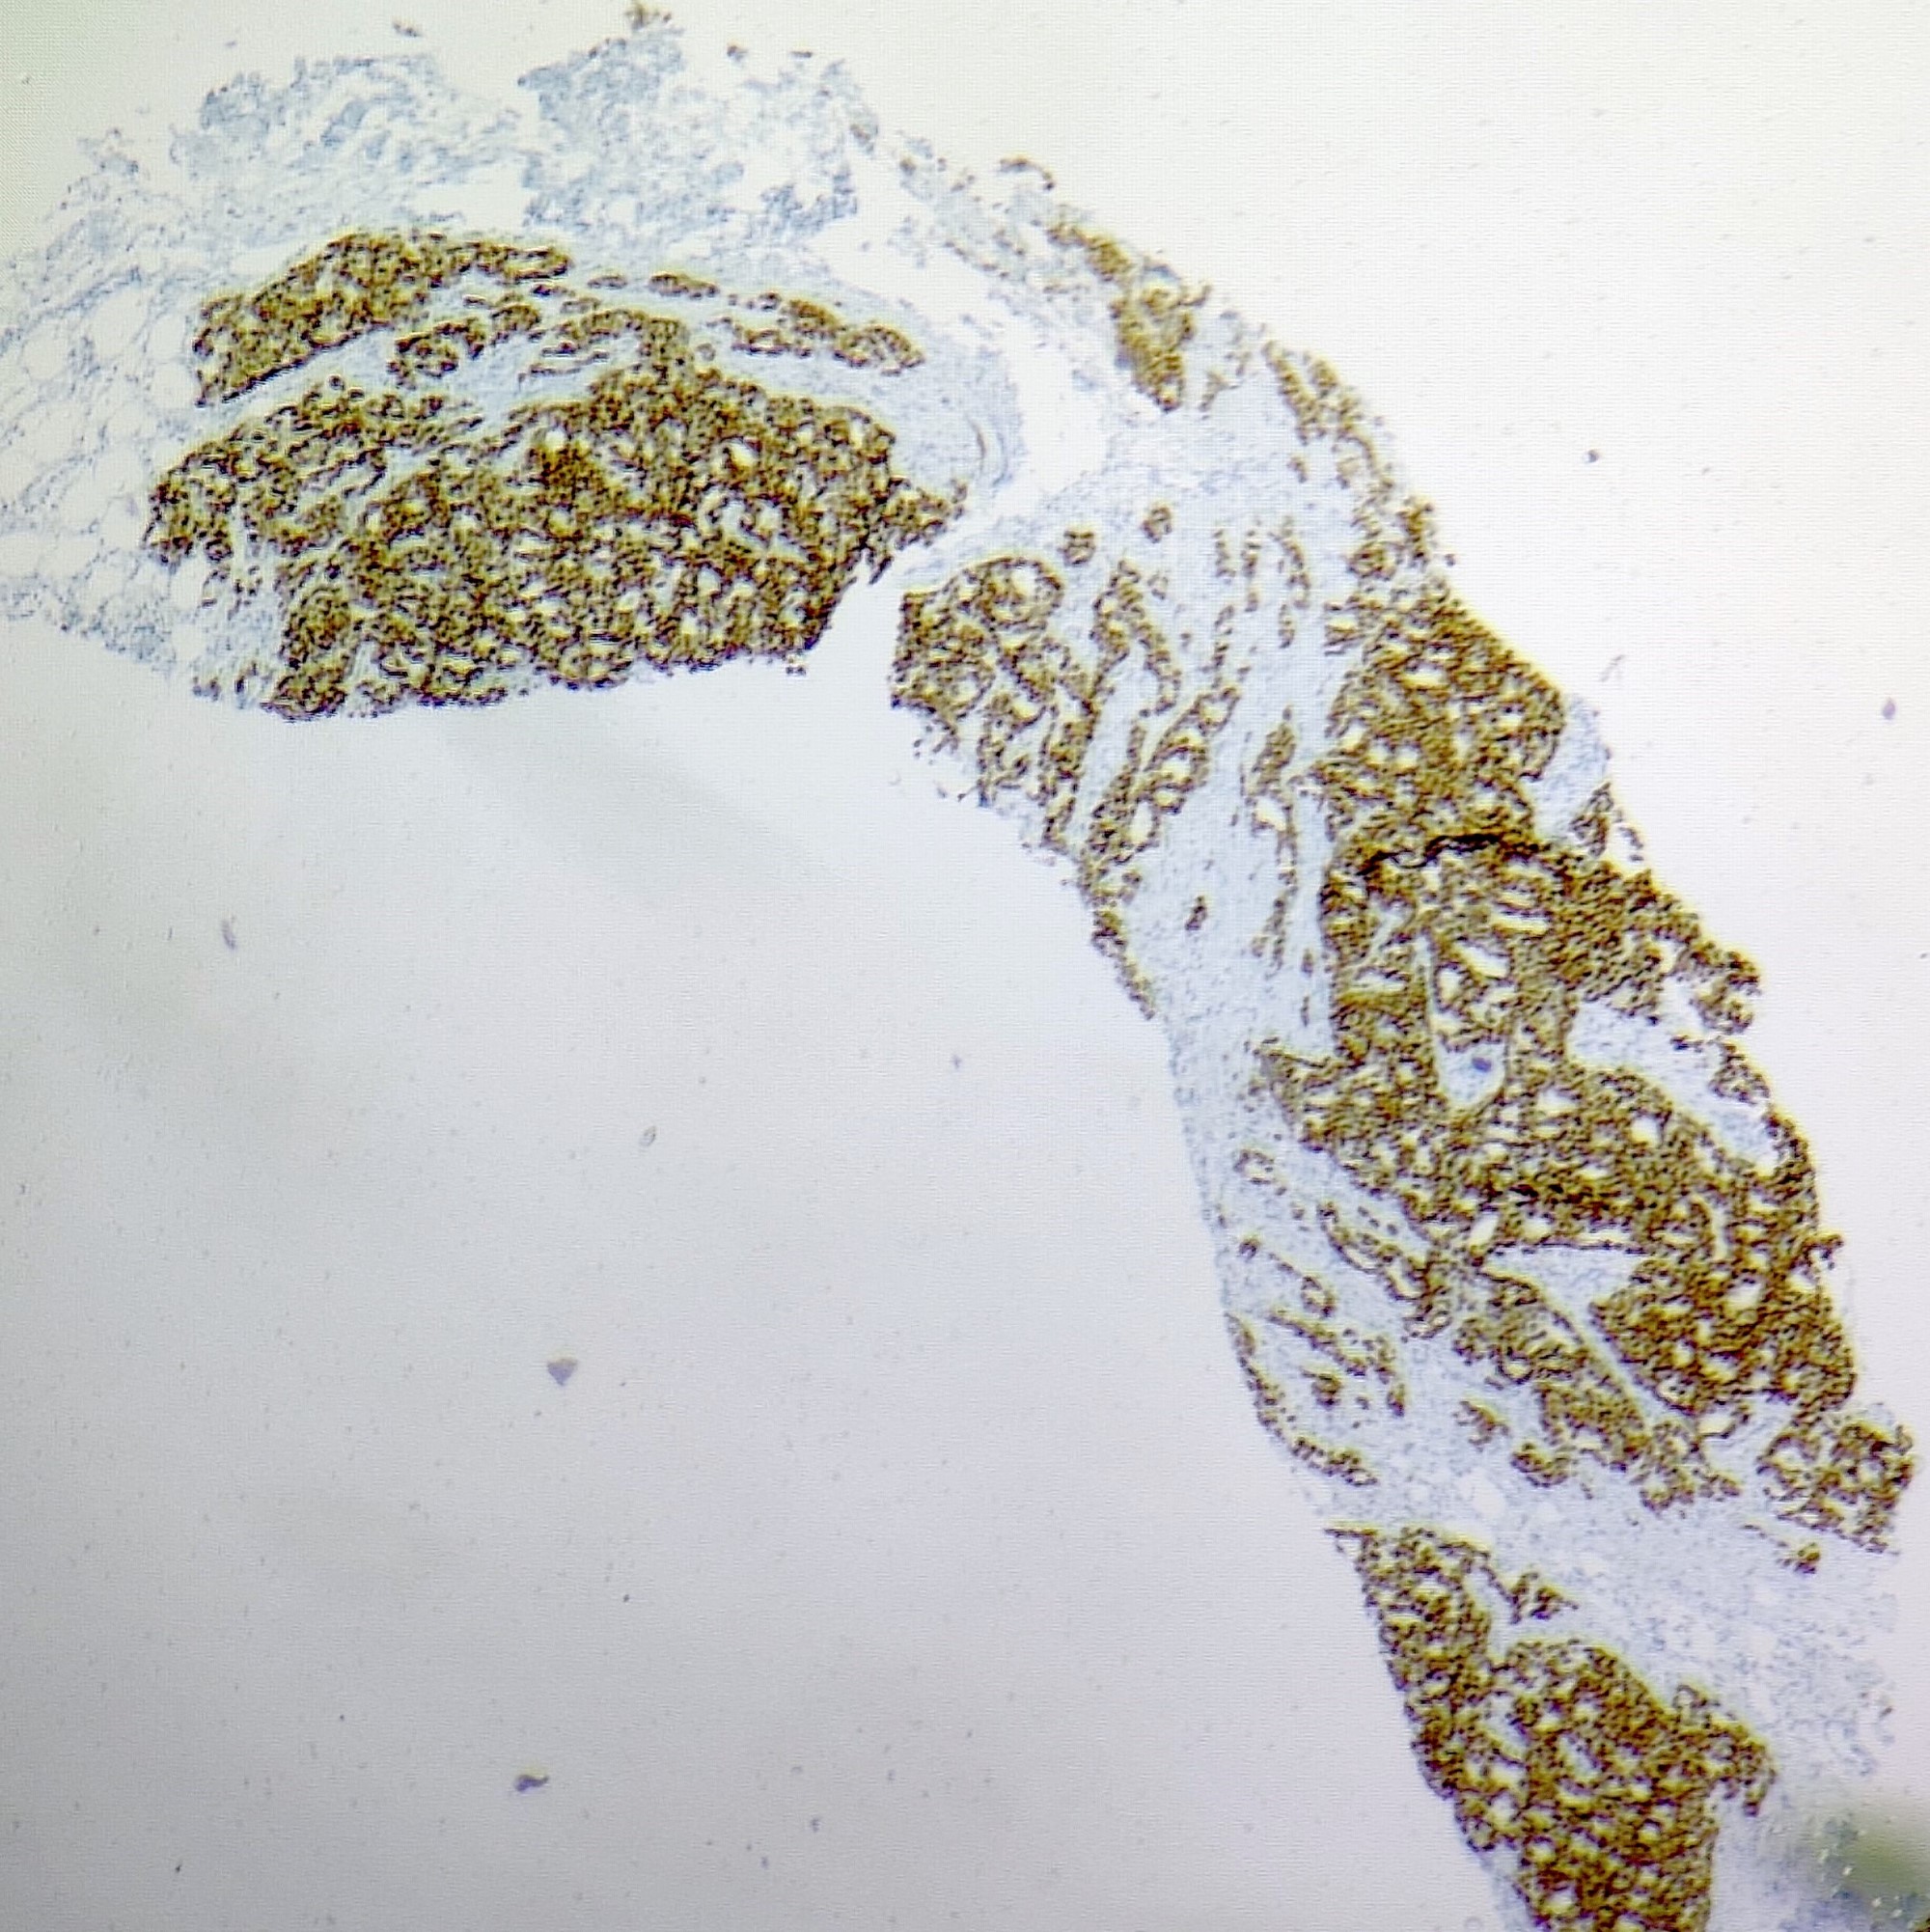

Microscopic (histologic) images

Contributed by Sunitha Shankaralingappa, M.B.B.S, M.D., D.M.

Microscopic (histologic) description

- Irregular cribriform growth pattern > 90% of cells

- Nuclear grade I pure ICC: > 90% cribriform pattern

- Mixed: 10 - 90% other morphological type, other than cribriform carcinoma

- Low grade: Nottingham grade 1 tumors

- Invasive islands or nests of malignant cells with round or angulated contours and well defined cribriform spaces formed by arches of epithelial cells; this gives a sieve-like appearance

- Tumor cells: small, mild / moderate pleomorphism, no nuclear atypia

- No / sparse mitotic activity

- Desmoplastic stroma

- Mucin positive secretion, microcalcifications in lumen

- Osteoclastic giant cells may be seen

- Myoepithelial cells absent

- Associated with cribriform ductal carcinoma in situ (DCIS)